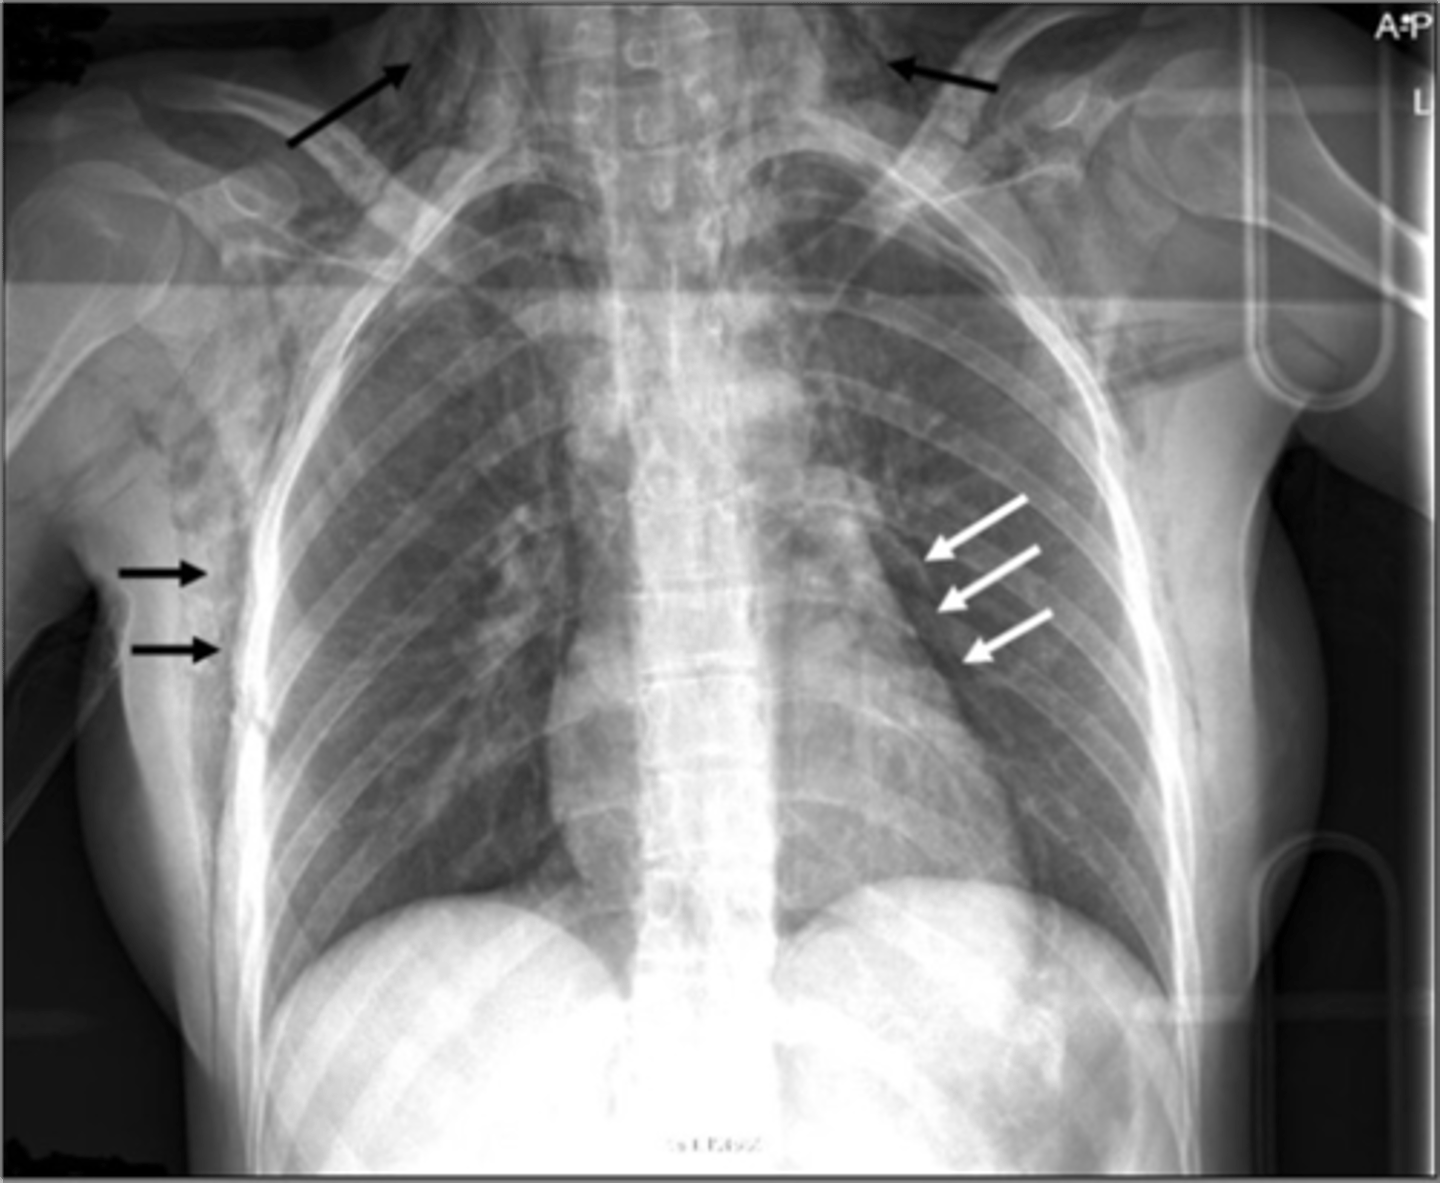

-atypical soft tissue mass in upper lobe of lung

-can see rib destruction or SVC obstruction

Pancost tumor appearance

white mass in hilar area

Hilar adenopathy appearance